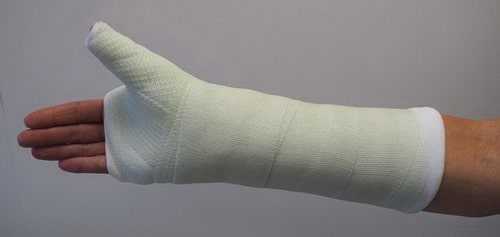

В среднем в зону ложного сустава вводили 3-5 порций костного трансплантата. После чего доводили две оставшиеся спицы в проксимальный отломок ладьевидной кости. Спицы скусывались подкожно. Далее на кожу накладывались швы, кисть фиксировалась в гипсовой лонгете.

Если перелом без смещения, то лечение выполняется без хирургического вмешательства. Как правило, это требует приведения иммобилизации (гипсования) лучезапястного сустава и первого пальца с небольшим отведением в течение 2 месяцев, пока перелом срастается. В некоторых случаях, пациенты с переломами без смещения просят выполнить операцию, чтобы уменьшить время иммобилизации и скорейшему восстановлению функции кисти. Такой подход по-прежнему несколько спорный среди хирургов-ортопедов.

Свежие переломы без смещения можно лечить без операции. Срок иммобилизации составляет не менее 10 недель. При наложении повязки фиксируют лучезапястный сустав и большой палец до межфалангового сустава.

При некоторых переломах ладьевидной кости для удержания фрагментов на период их заживления выполняется иммобилизация, включающая предплечье, лучезапястный сустав и большой палец.